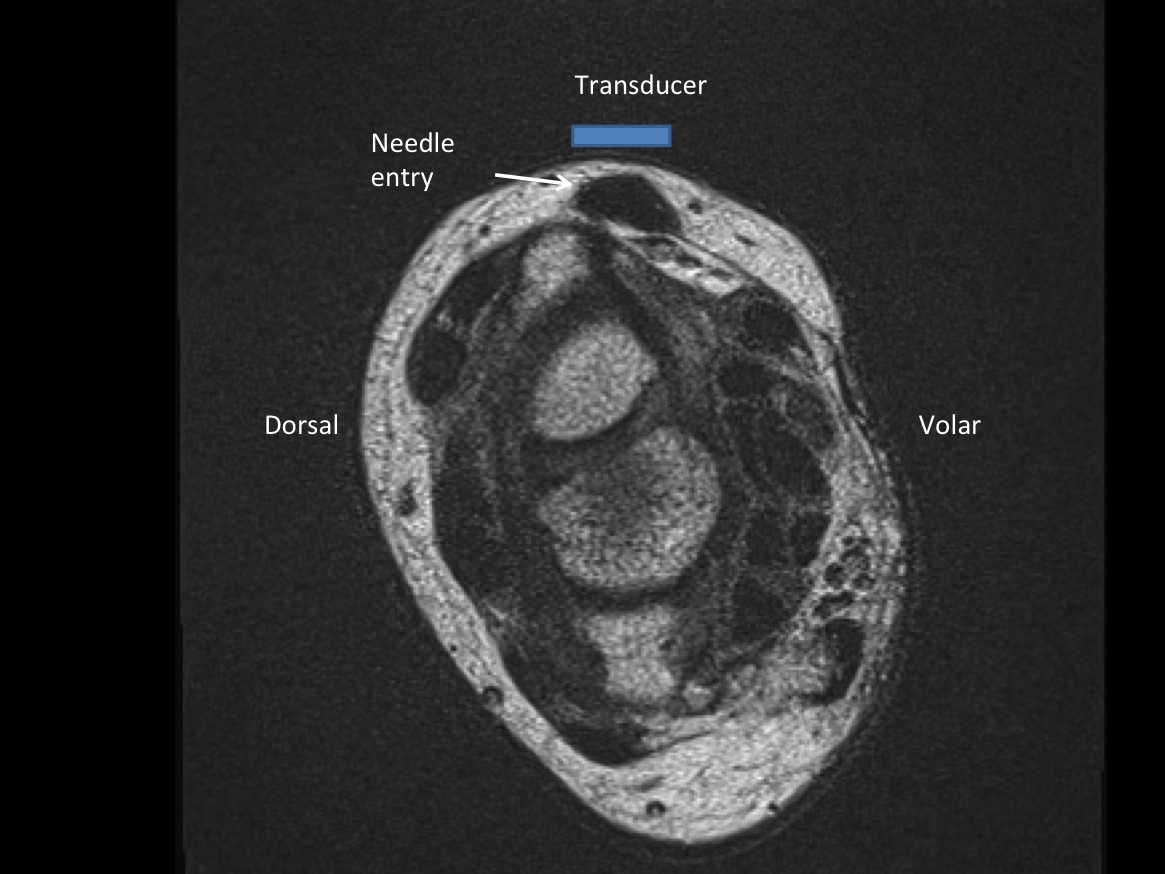

2. Position patient sitting with wrist supported by towel.

3. Place probe in short axis over first comparment extensor tendons-- Extensor pollicis brevis and abductor pollicis longus. description description

6. Inject 1% lidocaine superficially with 25g 1.5” needle. Advance needle deeper surface of the 1st extensor tendon sheath. Oftentimes, the APL and EPB tendons are in separate sheaths and may require separate injections. Then, unscrew syringe from needle for greater needle control.

7. Under ultrasound guidance,advance needle into the 1st extensor tendon sheath. In this case the APL and EPB have separate sheaths and require their own injections. Test inject with 1% lidocaine. If no resistance, switch 1% lidocaine for injectable steroid mixture. If there is resistance, reposition needle and test inject again. Inject 1 cc of injectable steroid/anesthetic mixture.